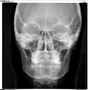

Telerradiografia Frontal

É uma radiografia lateral de crânio com uma distancia foco-filme maior e fixa de 1,5m , além disso utiliza-se os cefalostatos para posicionar o paciente de forma que seja possível a reprodutibilidade futura da mesma posição e seja possível fazer medições em ângulos formados por planos e linha. Nesta incidência são realizadas análises cefalométricas onde avalia-se o padrão dento-esqueletico- facial e o crescimento do crânio e da face.